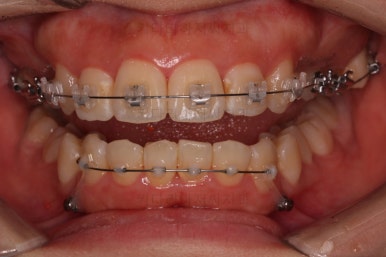

장치를 부착합니다.

이번 환자분이 선택한 장치는 엠파워 클리어라고 하는 자가결찰 세라믹 장치인데요.

철사를 묶는(결찰) cap이 장치에(자가) 달려있는 장치 중에 세라믹 성분으로 되어 심미성이 우수한 브라켓입니다.

대표적으로는 클리피씨 장치 등이 있습니다.

우선은 적응을 위해서 윗니만 장치를 부착하고요.

아랫니는 과개교합 개선을 위해 앞니 먼저 시작합니다.